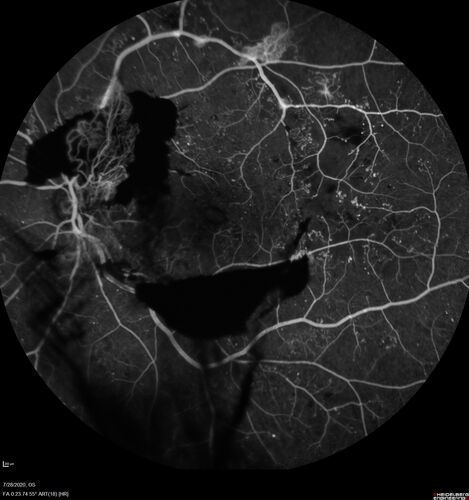

Proliferative Diabetic Retinopathy and vitreous hemorrhage left eye

44 year old man with type II diabetes for 14 years and no eye examinations in the last 5 years.  VA 20/40 right eye and 20/60 left eye.  Vision loss has been for about a week in the left eye.